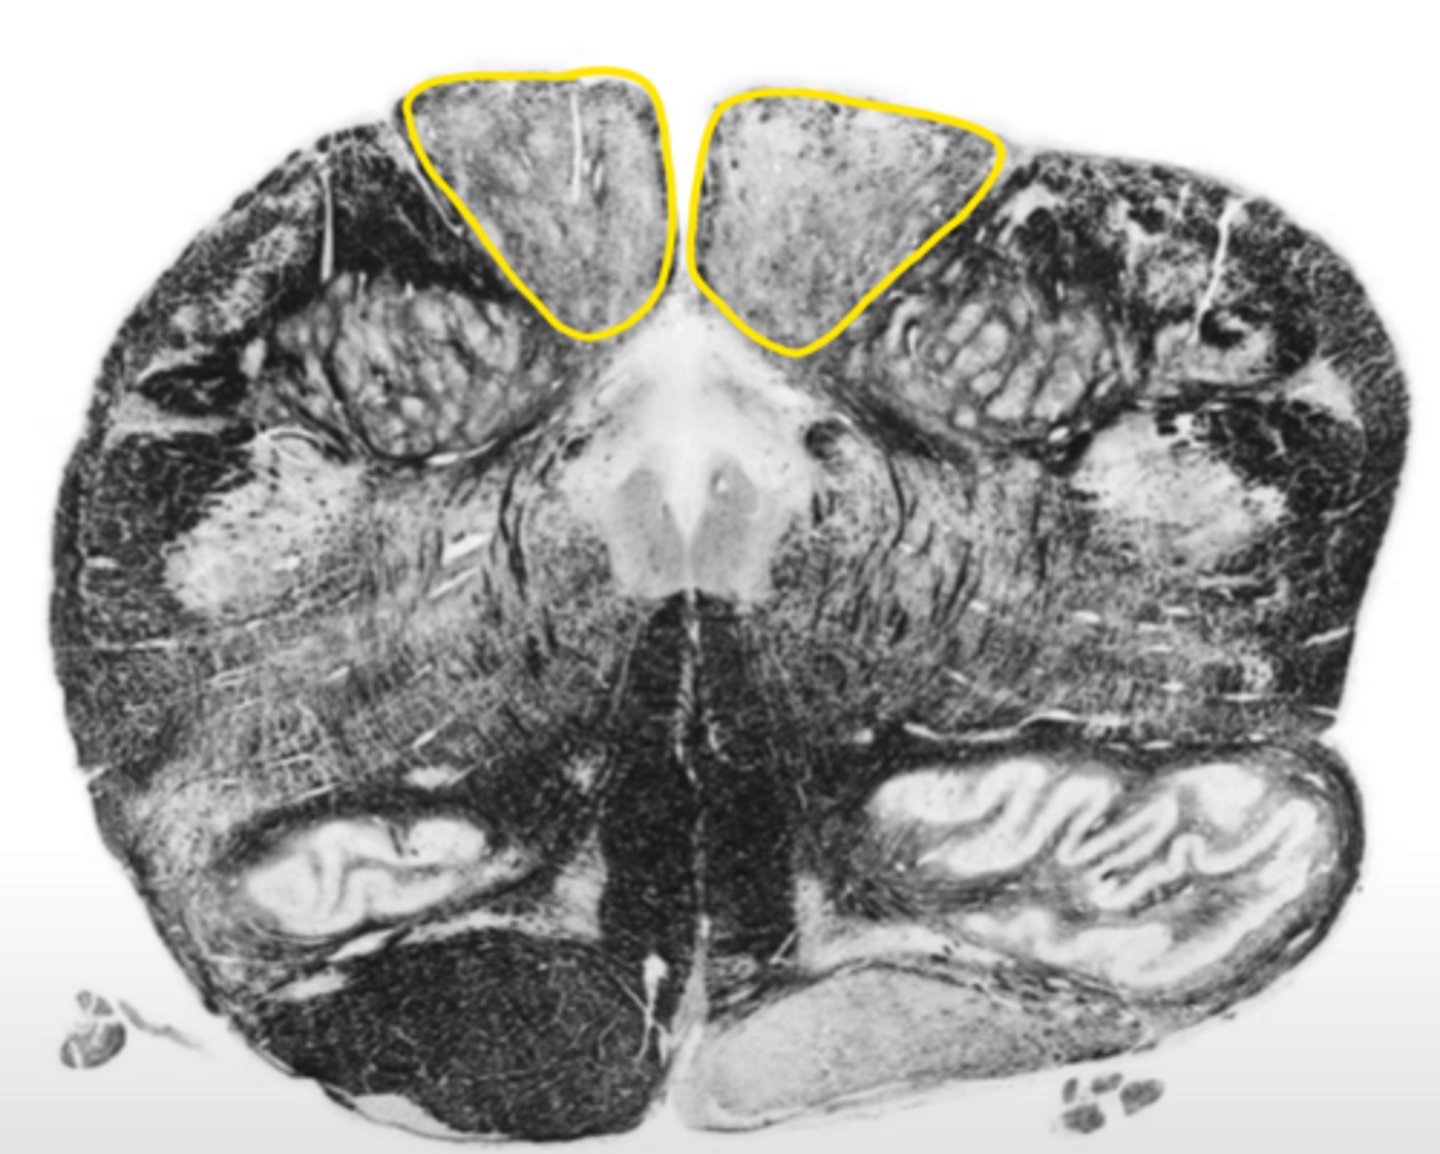

open medulla

ID the brainstem level